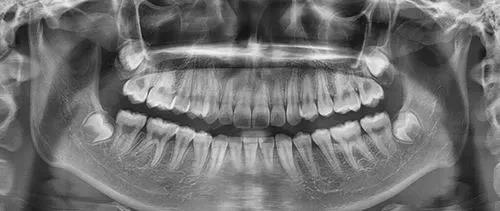

有患者说:“我只靠肉眼就能看出我的智齿是不是正常的,毕竟长歪长斜,还是能一眼就看出来的。”

不是这样,确实有一些智齿可以通过肉眼看出来,但只仅限于完全萌出的智齿或萌出大半部分的智齿。

对于只长出一小部分的智齿,仅凭肉眼即便能看出大概,也判断得不准确,无法完全看出病理状况。

完全没有萌出的智齿就只能去正规的医疗机构凭借牙片才能看出其生长状态,是否有阻生现象、对邻牙和牙神经是否有影响。

若有异常,医生可以根据牙片制定拔除方案,进而拔牙。